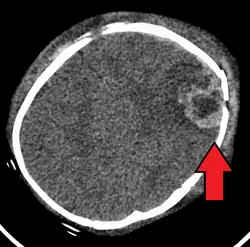

An intraparenchymal bleed with overlying skull fracture from shaken baby syndrome

Diagnosis can be difficult as symptoms may be nonspecific.[1] Symptoms may include altered mental status, trouble breathing, and vomiting.[7] As a result, about 31% of true SBS cases may go unnoticed initially. However, imaging can provide valuable information about a potential SBS diagnosis.[58] Imaging must be performed within at least 24 hours of the suspected injury to detect brain edema characteristic of SBS.[59] A CT scan of the head is typically recommended if a concern is present.[1] If there are concerning findings, a brain MRI is also recommended, which can further reveal parenchymal injuries and hemorrhages.[58] It is unclear how useful subdural haematoma, retinal hemorrhages, and encephalopathy are alone at making the diagnosis.[11]